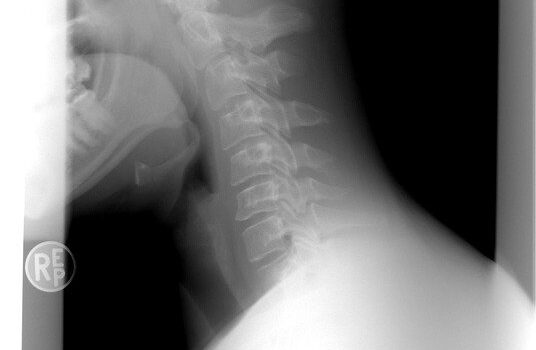

Treten wirbelsäulenbedingte Nackenschmerzen auf, spricht man von einem HWS-Syndrom. Die Schmerzen können dabei bis in die Arme, Hände und Schultern ausstrahlen. Ursächlich sind häufig degenerative Veränderungen der Halswirbelsäule. Aber auch andere Ursachen wie Verletzungen oder Fehlstellungen der Wirbelsäule (z. B. Skoliose) können Auslöser sein. Ein chronisches HWS-Syndrom entsteht meist durch plötzliche Überbeanspruchung. Z. B. […]